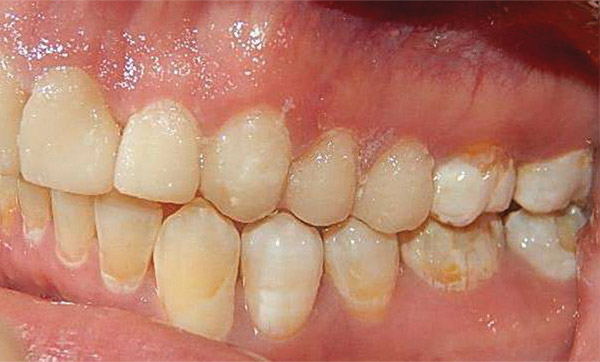

En las fotografías intraorales se muestra la fluorosis dental Tf4 y Tf7, las relaciones molares clase II molar y canina bilateral (Figura 3 y 4), el apiñamiento severo superior e inferior, con el órgano dental 35 en infraoclusión. El overbite aumentado y las líneas medias dentales no son coincidentes (Figura 5), las formas de arco superior e inferior son cuadradas (Figura 6 y 7).

Figura 3. Intraoral derecha.

Figura 4. Izquierda.